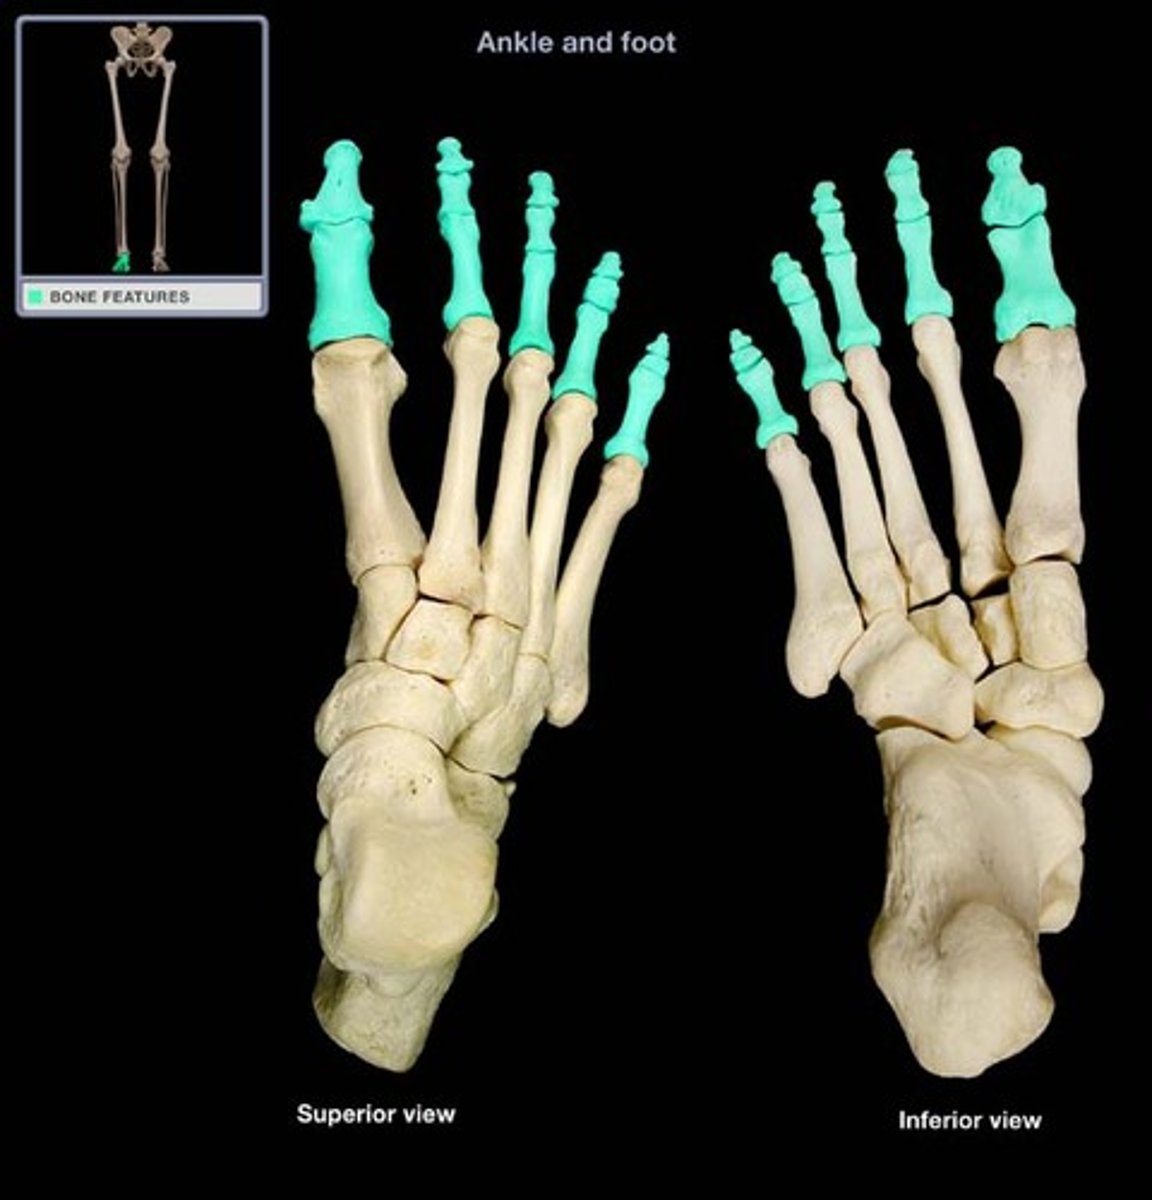

Digital

Fingers or toes

Tarsal

Ankle region

Calcaneal

pertaining to the heel